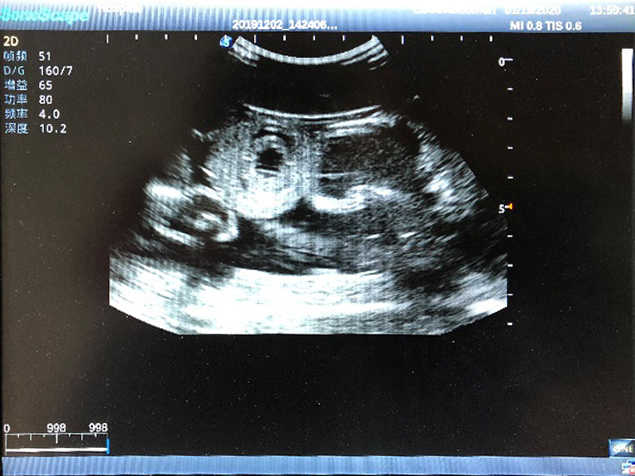

2)  High quality ultrasound image with clear structures like gallbladder, liver, intestines, arteries and veins etc.

5)  Normal & pathological ultrasound live and intestine models inside